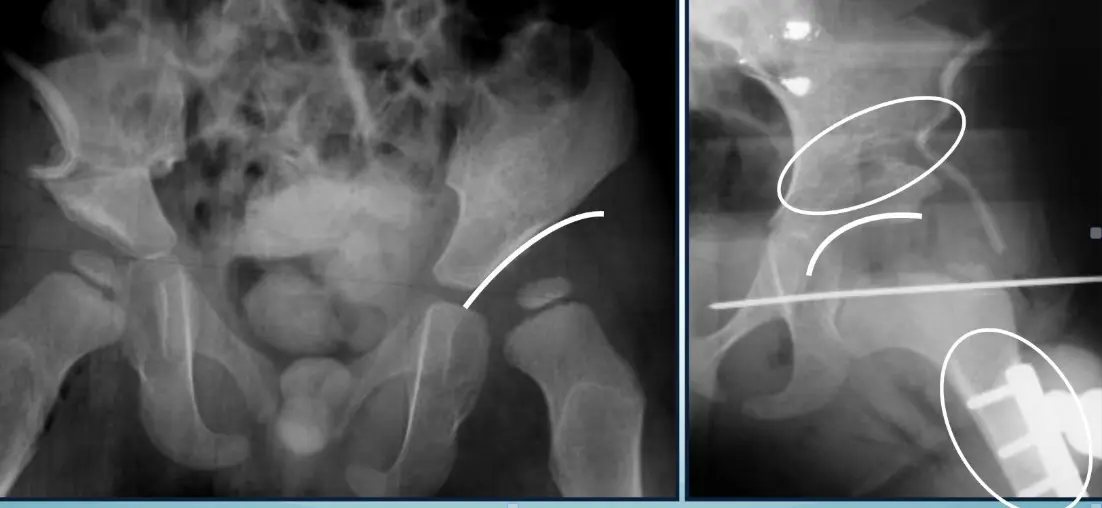

Case B: Pelvic Trauma

4.1) Open Book Fracture Management

1. Diagnosis? Answer: Open book fracture

2. Initial management? Answer: ATLS protocol, pelvic binder application

3. Mention 3 complications: Answer:

- Bleeding

- Pelvic instability

- Neurological injuries

4. Difference between stable and unstable management:

Stable open book fractures can typically be managed non-operatively, with the use of a pelvic binder or external fixation to stabilize the anterior pelvic ring until the injury heals.

Unstable open book fractures require surgical intervention to achieve anatomic reduction and stabilization of both the anterior and posterior pelvic rings.